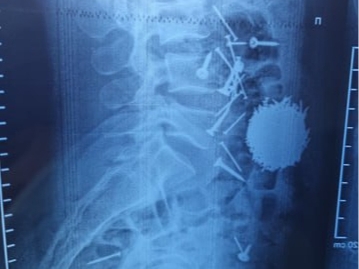

Samarqandda 29 yoshli fuqaroning qorin bo‘shlig‘idan 200 gramm mix va “samorez” olib tashlandi. Bu haqda Respublika shoshilinch tibbiy yordam ilmiy markazi Samarqand filiali xabar berdi.

Qayd etilishicha, muassasaga 29 yoshli fuqaro A.E. qorin sohasida kuchli og‘riq bilan keltirilgan. Shoshilinch qabul bo‘limida o‘tkazilgan diagnostika va laboratoriya tahlillariga ko‘ra bemorning me’da ichak tizimida katta miqdorda yot jismlar (mix va “samorez”) borligi aniqlangan.

Bemorda shoshilinch ravishda laparotomiya, gastrostomiya usulida jarrolik amaliyoti o‘tkazilib, qorin bo‘shlig‘idan mix va boshqa turdagi metal jismlar olib tashlangan. Hozirgi vaqtda bemorning ahvoli qoniqarli.